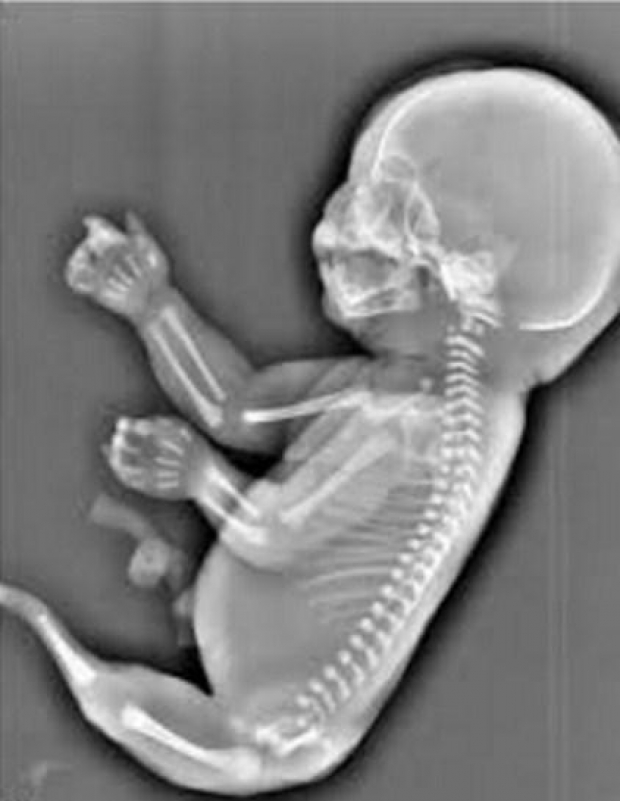

Sindroma “Mermaid” është një deformim i rrallë te këmbët, të cilat janë të bashkuara e marrin pamjen e një bishti që rritet njësoj si i sirenës dhe ndodh 1 në 100 shtatazani.

23-vjeçarja, Wu, ishte 6 muajsh shtatzënë, kur ekoja e Wu, tregoi se fëmija i saj i palindur, nuk kishte dy këmbë, por në vend të tyre kishte një “bisht”, që rritej.

Mjekët e spitalit i thanë Wu, se fetusi po vuante nga një gjendje e njohur si sirenomelia, ose sindroma ‘Mermaid’.